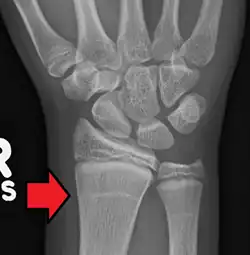

Harris-Linien sind Linien höherer Knochendichte, die im Röntgenbild erkennbar sind. Sie verlaufen parallel zur Epiphysenfuge in der Metaphyse langer Knochen – insbesondere des Schienbeines (Tibia) – und sind ein Zeichen für eine kurzzeitige Veränderung im Längenwachstum der Knochen. Im englischen Sprachraum sind die Bezeichnungen Harris lines, growth arrest lines, recovery lines, stress lines, Park-Harris growth arrest lines oder auch Park lines im Gebrauch. Der Name geht auf den Erstbeschreiber, den walisischen Anatomen Henry Albert Harris, zurück bzw. auf Edwards Albert Park (1877–1969).

Als Ursachen von Harris-Linien werden oft Vitamin- oder Nahrungsmangel (zum Beispiel bei Krankheit oder Unterernährung) oder längere Immobilität genannt; danach soll es nach Wachstumsstillständen zu einem folgenden Aufholwachstum mit einer veränderten Knochenneubildung kommen, die als quer verlaufender röntgendichter Streifen zu erkennen ist. Einmal angelegte Harris-Linien können rückgebildet werden und ihre Sichtbarkeit verlieren. Die Deutung von Harris-Linien als Anzeiger von Mangelernährung ist umstritten; neuere Studien legen dar, dass Harris-Linien nicht durch Mangelernährung entstehen, sondern eine wohl übliche Erscheinung beim Knochenwachstum von Kindern und Jugendlichen sind.